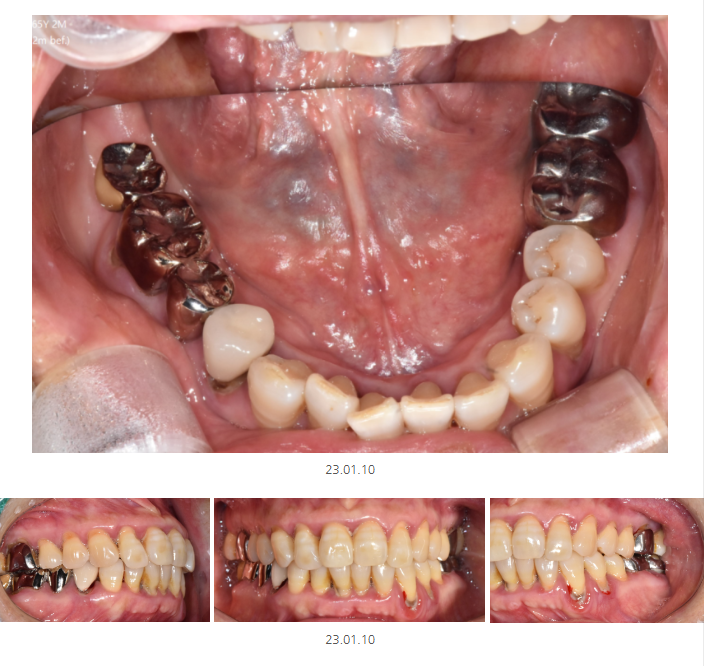

처음과 치료 후 사진 말고도

천호동 치과는 치료 중간에도 사진을 남겨둡니다.

해당 환자분은 보철을 벗겼더니

충치가 있는 것을 찍어둔 사진입니다.

치아 상태가 이래서 치료를 할 수 밖에 없었다

최대한 자세히 설명드리고 싶거든요~